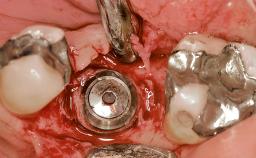

Early Placement of an Implant in a Maxillary Right Central Incisor Site

This 41-year-old female patient was referred to the clinic for the replacement of the right central incisor, since the tooth had developed a root fracture in the long axis that made extraction necessary. The healthy, non-smoking patient was first seen with the tooth still in place. A detailed Esthetic Risk Assessment was performed.The patient was worried about her dental esthetics and had high expectations for a successful treatment outcome from an esthetic point of view. The patient had a medium lip line that displayed parts of the gingiva in the anterior maxilla upon smile.

Bone Augmentation Horizontal|Simultaneous

Augmentation Materials Autogenous chips|Xenogenous|Membrane

Bone Volume Deficient horizontally, allowing simultaneous augumentation